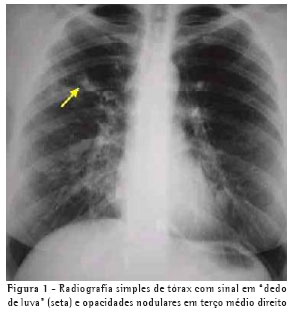

A avaliação clínica revelou roncos e sibilos difusos bilaterais. Os exames subsidiários mostraram: espirometria normal, teste alérgico cutâneo imediato (Prick teste) positivo para A. fumigatus, hemograma com eosinofilia (13%), IgE sérica total maior que 1.000 ng/ml, teste sérico para determinação de IgE específica (RAST) para A. fumigatus classe 3. Na radiografia simples de tórax observaram-se imagens de opacidade em "dedo de luva" no terço superior direito (Figura 1) e na tomografia computadorizada de alta resolução, bronquiectasias centrais (Figura 2).

De acordo com os achados de inúmeros trabalhos, as alterações observadas na radiografia de tórax de pacientes com ABPA têm sido descritas como imagens de consolidações extensas e de infiltrado alveolar, que ocorrem predominantemente nos lobos superiores, e imagens que espelham impactação mucóide num brônquio central. A imagem em "dedo de luva" e a imagem em "pasta de dente" são imagens transitórias de impactação de muco que podem desaparecer com a tosse ou com o uso de corticóide.(7-9) A paciente apresentou, na radiografia simples de tórax, sinais de opacidade em "dedo de luva" no terço superior do hemitórax direito (Figura 1) e, na tomografia computadorizada de alta resolução, sinais de bronquiectasias centrais (Figura 2). Segundo a literatura, sinais de opacidade em "dedo de luva" são sugestivos de ABPA,(10) refletindo a inflamação, espessamento e dilatação da árvore brônquica, devidos à impactação de muco nas vias aéreas.(11) Para a detecção de bronquiectasias centrais, a tomografia computadorizada de alta resolução é sugerida como o melhor método diagnóstico, tendo em vista que, para essa finalidade, a radiografia de tórax não é sensível e nem específica.(4)